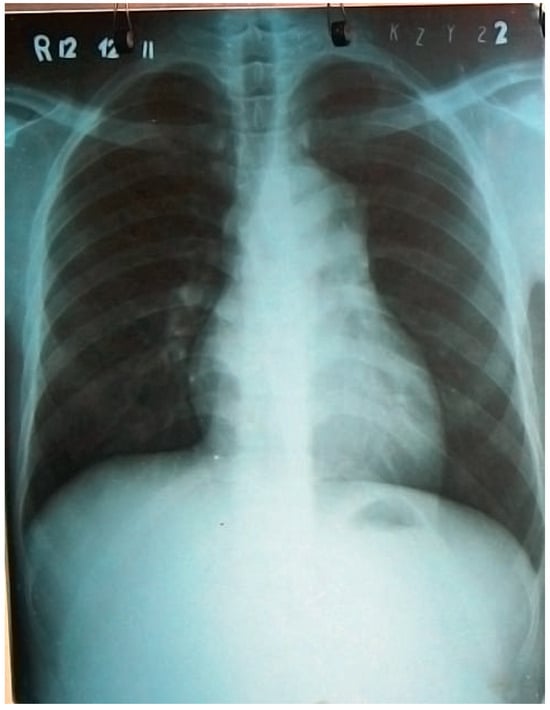

At Yangon Medical University, clinical and echocardiographic findings were confirmed. In addition, chest X-ray revealed a cardiothoracic ratio at its upper limit, but was otherwise found to be normal (Figure 1). Diuretic therapy was introduced and the patient temporarily improved.

Figure 1. First chest X-ray without any evidence of a major thoracic aortic injury.